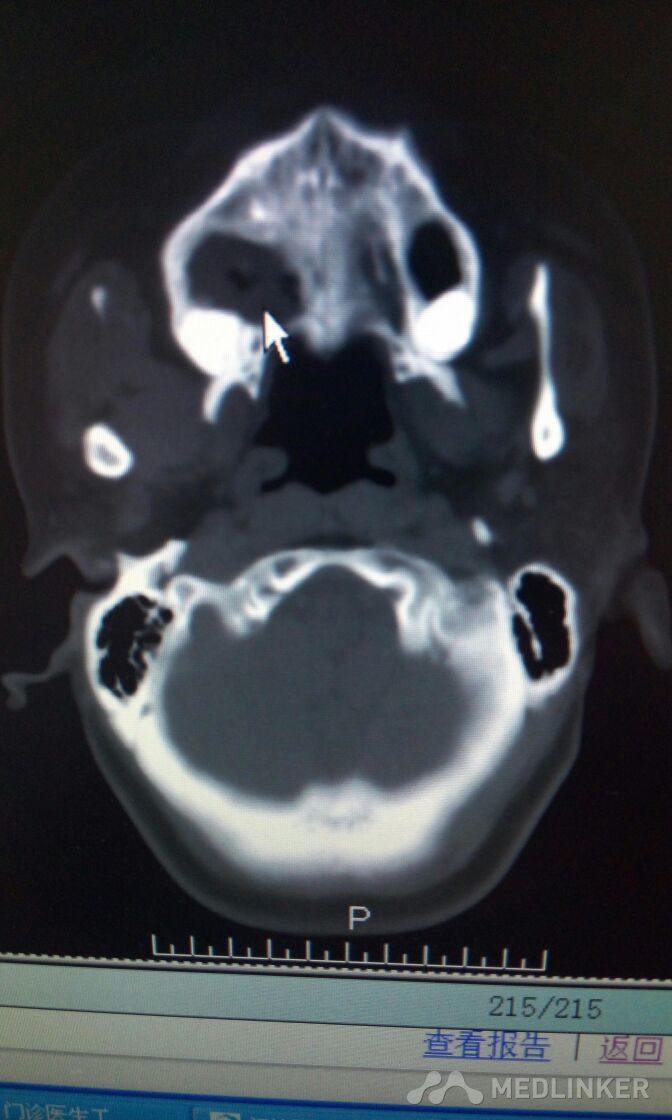

患者,女,38岁。因“发现右侧腭部肿痛一周”,来诊。查体:颌面部对称,张口度好。腭部右侧可见粘膜凸起肿物,约2*3cm,近中线处溃烂,有溢脓。CT检查可见肿物突入上颌窦及鼻腔,骨质破坏。现应用抗菌素治疗。拟行病理活检。请同仁看看手术方案?患者年轻,一侧上颌骨去除,假体如何修复?可否请鼻科联合手术,保留颌骨?

看看这个上颌窦